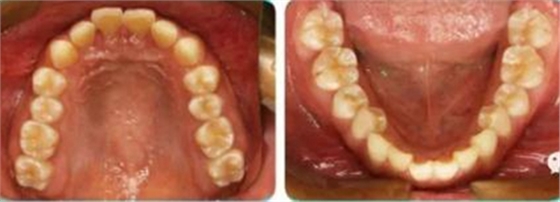

正面觀雙側(cè)面型基本對稱,側(cè)面觀上頜凸、下頜后縮,頦唇溝深。

恒牙列,上下牙列中線對齊,前牙深覆合、深覆蓋均為Ⅲ°。雙側(cè)磨牙、尖牙為Ⅱ類遠(yuǎn)中關(guān)系,A4C4、B4D4正鎖合。

全口曲斷顯示A1B1根尖存在吸收。